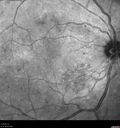

43 year old man He has had laser in both eyes for bleeding. At the moment the vision is blurry in both eyes. The left one is a little bit worse than the right eye. He also started using reading glasses. VA OD: sc20/32-1 NscJ1-2 VA OS: sc20/40-1 NscJ5-1 IOP: TP: OD:15 OS:15

Moderate PDR408 views43 year old man 20/32 vision in both eyes. Being started on Anti-VEGF injections which will be followed by PRP.00000